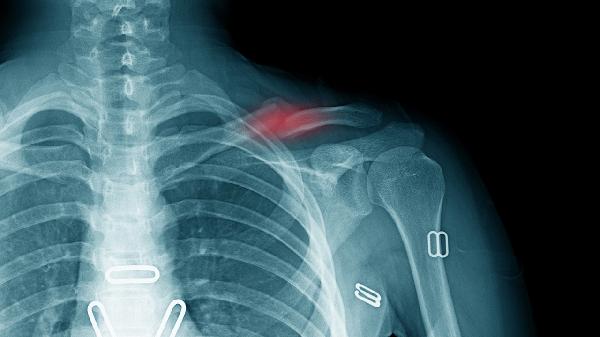

骨折后1周、4周、8周分别进行X线检查,观察骨痂生长情况。若出现内固定松动、延迟愈合等异常,需及时干预。复查时携带既往影像资料便于对比。